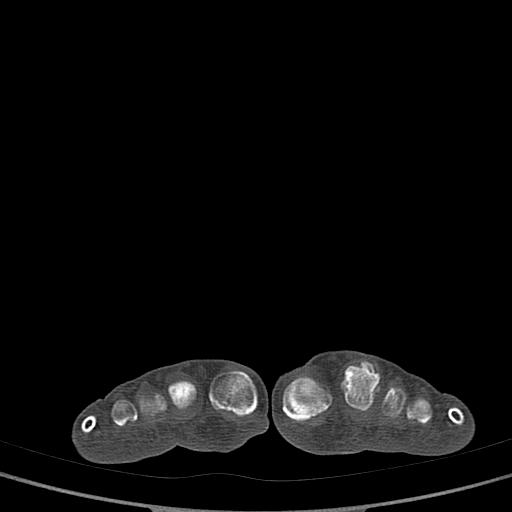

骨软骨瘤可能性大,请上传x光片.

不象软骨瘤,

考虑退行性骨关节病。